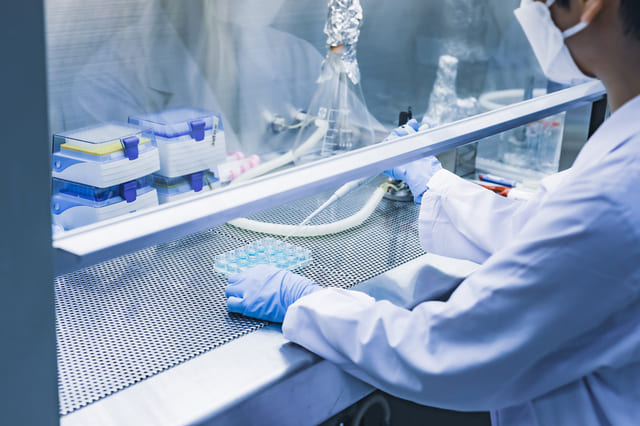

無菌室設備の紹介

Sterile room equipment

当院では厳密な無菌状態を維持するために特別な「無菌室」を設けています。

- 無菌室内作業風景

- 無菌室内作業風景

- 無菌室内

- 無菌室内

- 無菌室内

感染リスクの低減・品質保持

当院の無菌室は、細菌やウイルス、微生物からの汚染を防ぐために特別に設計されています。

また、無菌室を有することは、薬剤の品質を維持するため、または免疫抑制を伴うがん患者様にとって重要となります。